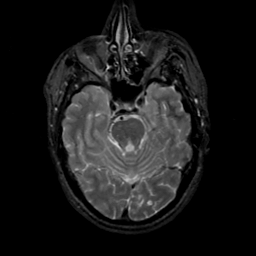

MR Study #17, July 7, 1991 -- Slice #16